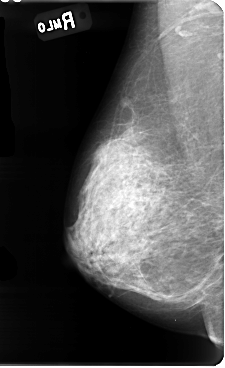

B_3085_1.LEFT_MLO

RIGHT_MLO LINES 4784 PIXELS_PER_LINE 2920 BITS_PER_PIXEL 12 RESOLUTION 50 NON_OVERLAY